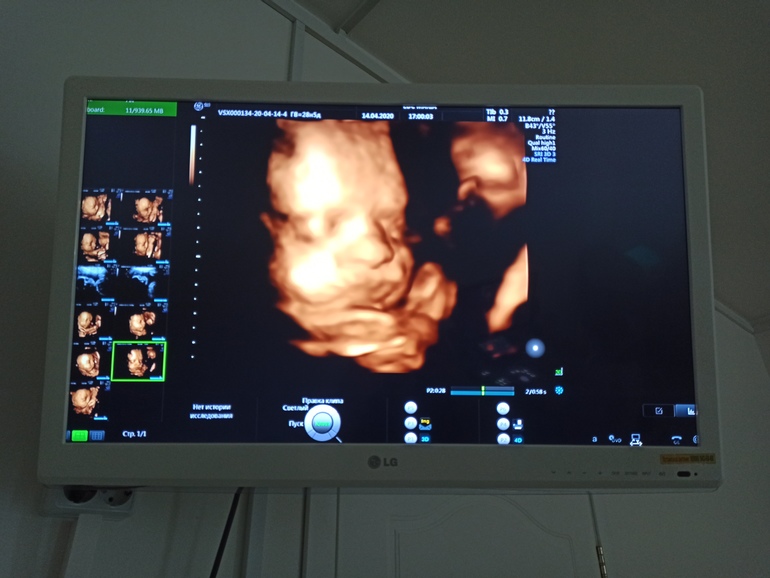

3D УЗИ: малыш прелесть, а мама развалюха-ха)

Здоровый образ жизни, питание Сегодня не удержалась, сходила на 3Д УЗИ - без измерений, только видео на память. Скоро третий скрининг, недели через 3, а допплер сосудов и шейку матки я недавно мерила.

Сегодня не удержалась, сходила на 3Д УЗИ - без измерений, только видео на память. Скоро третий скрининг, недели через 3, а допплер сосудов и шейку матки я недавно мерила.

К сожалению, дисков у них в наличии не оказалось, пришлось снимать с экрана) Ну и ладно, зато малыш, наконец, перевернулся вниз головой, а то до этого 3 раза на УЗИ сидел на попе. Закрывался ручкой, зевал, высовывал язык, улыбался - для меня всё это было настоящее чудо)